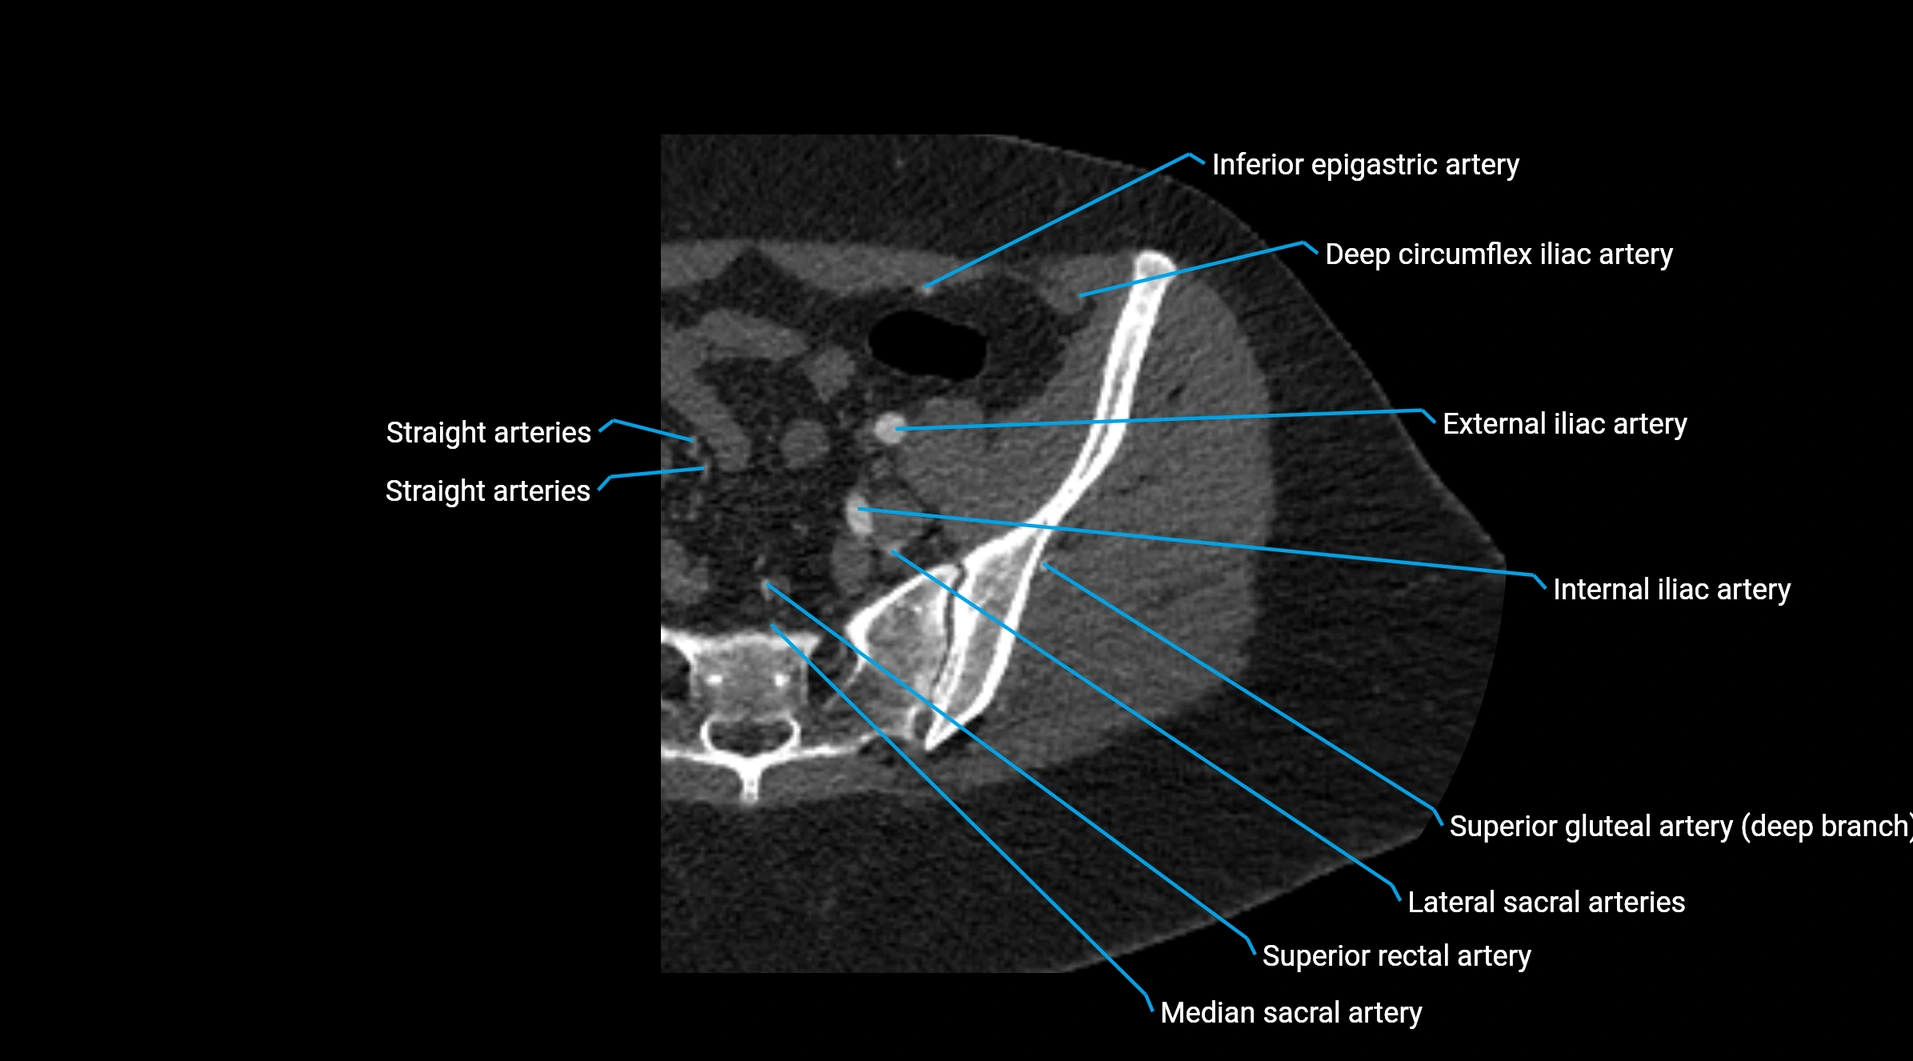

Contrast-enhanced CT (CTA):

• Gold standard for abdominal aortic imaging

• Provides excellent detail of lumen, wall, aneurysm, thrombus, and branch vessels

• Multiplanar and 3D reconstructions help in aneurysm measurement, stent graft planning, and dissection evaluation

• Detects acute rupture, traumatic injury, or occlusion with high sensitivity